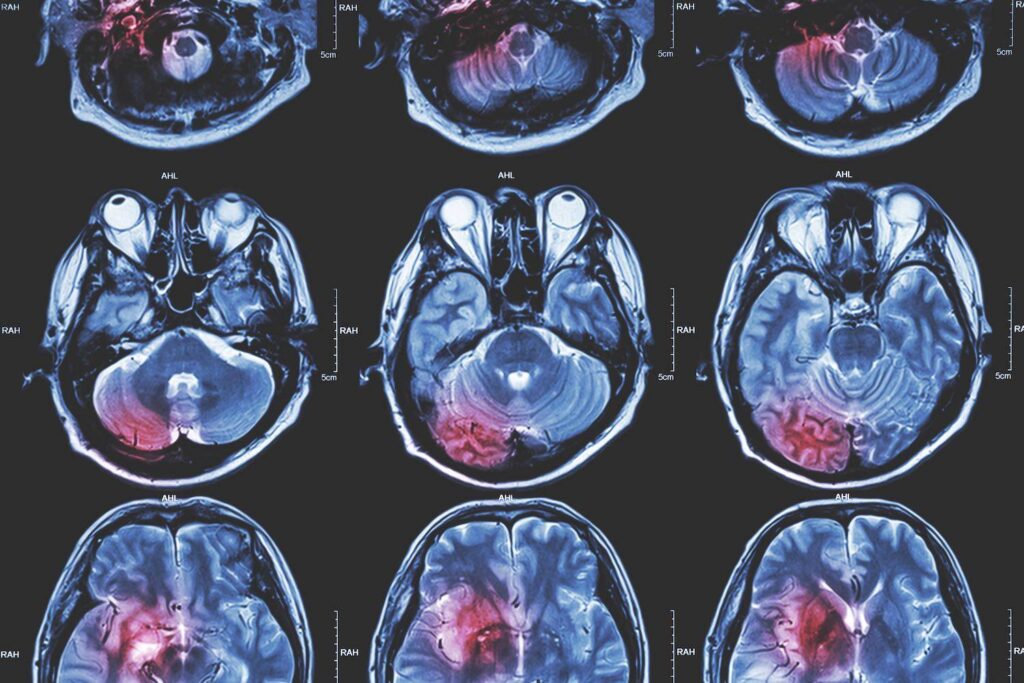

Es gibt Fälle, in denen eine Person das Aussehen oder die Existenz eines Tumors sehen oder fühlen kann, aber in manchen Situationen sind diese nur bei Untersuchungen sichtbar, einschließlich der Magnetresonanztomographie (MRT). Je nach Ergebnis kann es notwendig sein, eine Biopsie durchzuführen, d. h. eine kleine Gewebeprobe zu entnehmen, die unter dem Mikroskop untersucht wird.

Wie sieht ein Tumor im MRT aus?

Die MRT eignet sich zur Erkennung von Tumoren und Metastasen und liefert ein klares Bild der Knochen- und Weichteilstrukturen. Ein Tumor hat die Form eines abnormen Knötchens oder Zellhaufens;

Tumor im Kopf

Zu den häufigsten Hirntumoren gehören die Meningoide, die durch Behandlung oder Operation behandelt werden können. In den meisten Fällen ist der Tumor gutartig, muss nicht entfernt werden und breitet sich nicht auf andere Organe aus. Bei einem Hirntumor handelt es sich um eine abnorme Vermehrung von Zellen im Gehirn, von denen einige krebsartig sein können, während andere nicht lebensbedrohlich sind.